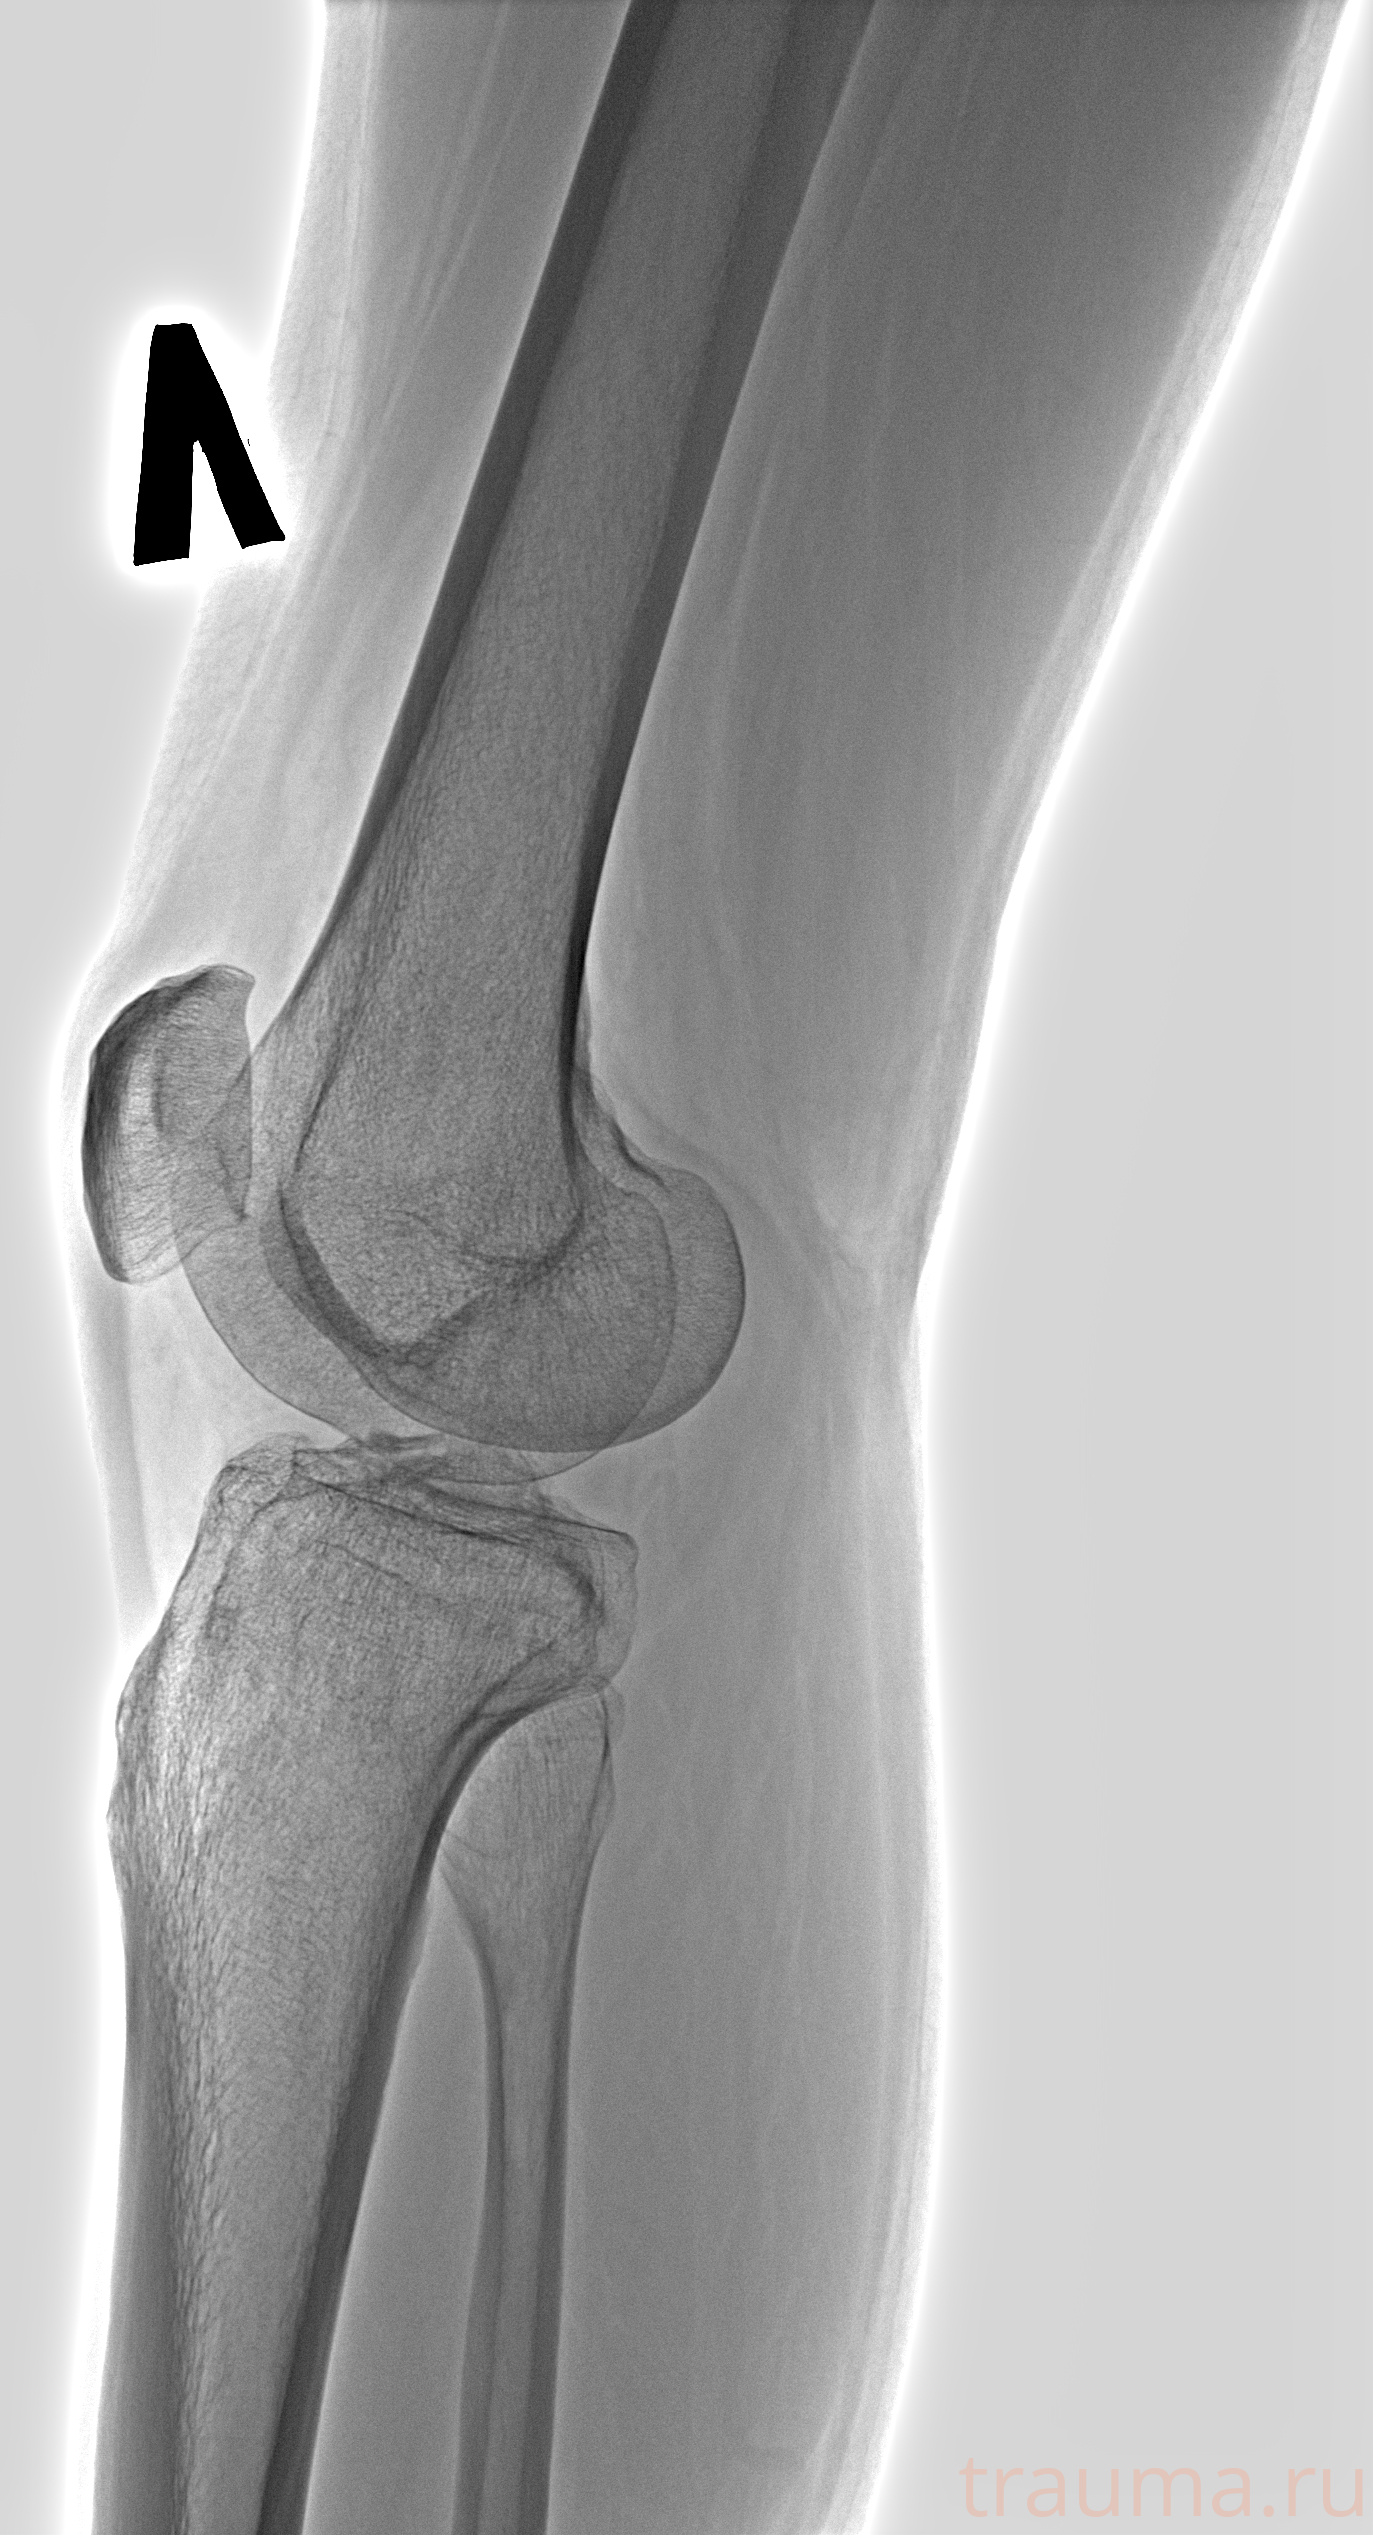

Рентгенограммы